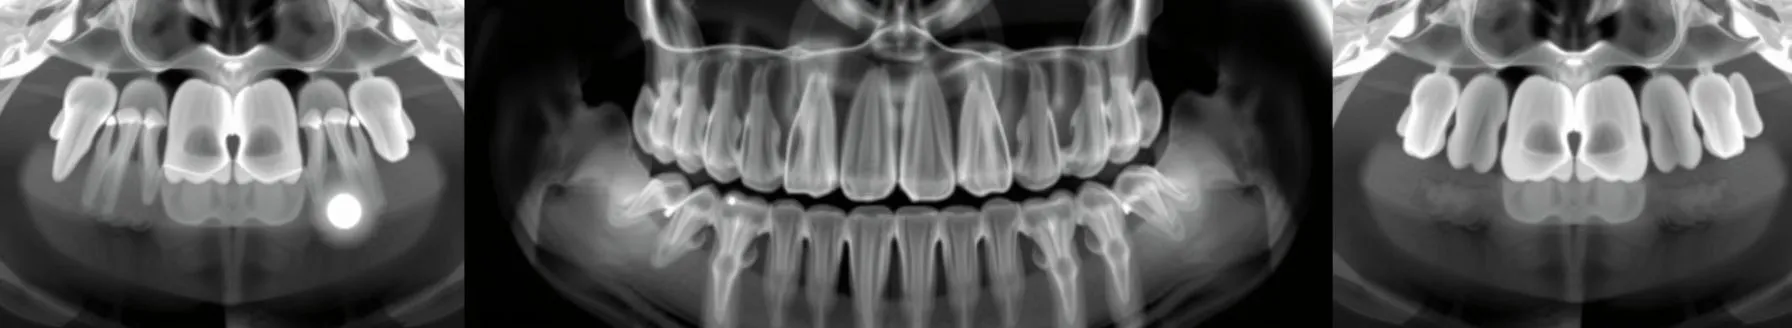

Diagnostic radiology includes defining and differentiating various normal structures in addition to establishing the existence and kind of pathosis. It also requires determining root and pulp anatomy. Not only must the roots and canals be recognised and counted, but also atypical tooth structure,...

- Preoperative radiographs are crucial in endodontics, but dentists often misjudge them, leading to root canal failures. Dentists need to carefully analyze these radiographs to avoid errors and ensure treatment success.